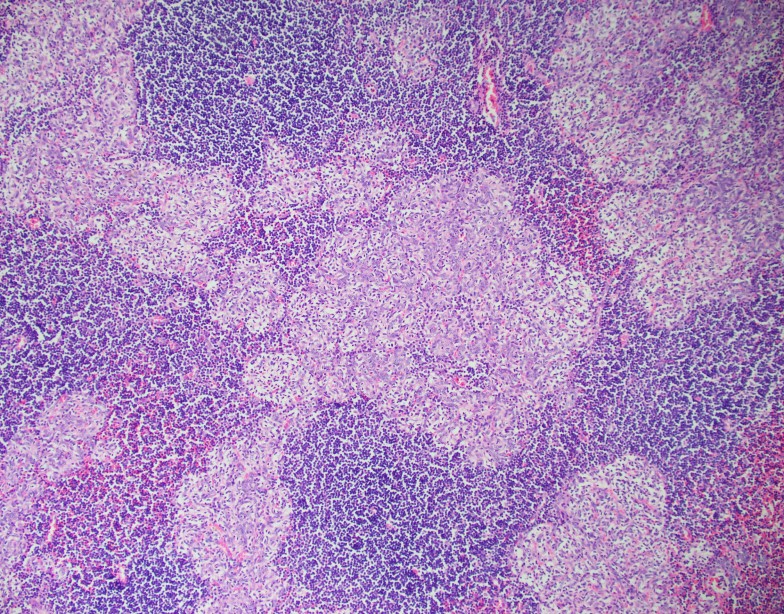

Tissue sections show a diffuse atypical lymphoid infiltrate that completely effaces the normal nodal architecture. The infiltrate is composed of numerous small lymphocytes with round to mildly irregular nuclei, clumped chromatin, inconspicuous nucleoli and scant cytoplasm. There are also expanded pale areas that contain intermediate sized cells with more open chromatin and distinct single to multiple nucleoli. These cells are most consistent with prolymphocytes/paraimmunoblasts and form the proliferation centers characteristic of CLL/SLL. Occasional centroblastic-type B-cells are noted within these proliferation centers. In addition, there are scattered single to multinucleated cells that have irregular nuclear membranes with pale, vesicular chromatin and prominent inclusion-like, eosinophilic nucleoli. These cells morphologically resemble Hodgkin cells, Reed-Sternberg cells, mummified forms and other variants. These large cells are more evident in areas with a histiocyte rich background and around foci of necrosis. Occasionally, apoptotic bodies and mitotic figures are seen.

The morphologic and immunophenotypic findings are consistent with involvement by the patient’s known small lymphocytic lymphoma/chronic lymphocytic leukemia (SLL/CLL) with aggressive morphological features. The aggressive features include expanded proliferation centers and an elevated Ki-67 proliferative index (40%). Additionally there are histiocyte/T-cell rich areas composed of multiple EBV positive large atypical cells with morphologic and immunophenotypic features compatible with Hodgkin/ Reed-Sternberg cells. These areas are most in keeping with evolving classic Hodgkin lymphoma. Sheets of large cells indicative of large cell transformation are not seen, although increased scattered large centroblastic-type B cells are present.

Lymph node involvement by CLL/SLL will typically show a diffuse proliferation of small lymphocytes with effacement of the normal nodal architecture. The small lymphocytes have round nuclei, clumped chromatin and scant cytoplasm. Scattered paler areas known as proliferation centers are characteristic of this entity. The proliferation centers are composed of a mixture of cell types including small lymphocytes, prolymphocytes and paraimmunoblasts. Prolymphocytes are small to medium in size with relatively clumped chromatin, whereas paraimmunoblasts are larger cells with round to oval nuclei, dispersed chromatin, eosinophilic nucleoli and slightly basophilic cytoplasm. Some cases show increased and enlarged proliferation centers with a higher proliferation rate. This must be distinguished from large cell transformation.1

Aggressive features of CLL/SLL include proliferation centers that are broader than a 20x field or becoming confluent. An increased Ki-67 proliferation >40% or >2.4 mitoses in the proliferation centers can also portend a more aggressive course. These cases tend to have worse outcomes than typical CLL/SLL and better outcomes than cases that have undergone Richter transformation to diffuse large B-cell lymphoma (DLBCL). Transformation to DLBCL occurs in 2-8% of patients with CLL/SLL. Less than 1% of patients with CLL/SLL develop classic Hodgkin lymphoma (CHL). In order to diagnose CHL in the setting of CLL/SLL, classic Reed-Sternberg cells need to be found in a background appropriate for CHL, which includes a mixed inflammatory background. The majority of these CHL cases will be positive for EBV.1